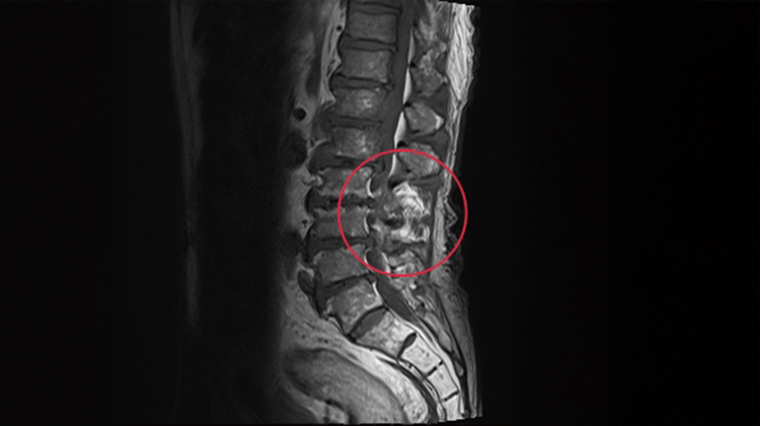

▲婦人經核磁共振檢查後,確診是腰椎第2、3節骨髓炎。(圖/亞洲大學附屬醫院提供)

直到後來因患者疼痛症狀加劇,就醫後建議改掛感染科,詢問相關症狀後,當下便懷疑可能是「脊椎骨髓炎」引起,隨即安排患者住院及接受電腦斷層與核磁共振檢查,隨即確診是腰椎第2、3節骨髓炎,後續血液培養結果也發現鏈球菌指數偏高,原來是「細菌跑到骨頭裡面了」。